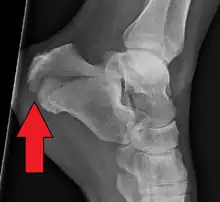

Conventional radiography is usually the initial assessment tool when a calcaneal fracture is suspected. Recommended x-ray views are (a) axial, (b) anteroposterior, (c) oblique and (d) views with dorsiflexion and internal rotation of the foot. However, conventional radiography is limited for visualization of calcaneal anatomy, especially at the subtalar joint. A CT scan is currently the imaging study of choice for evaluating calcaneal injury and has substituted conventional radiography in the classification of calcaneal fractures.[13] Axial and coronal views are obtained for proper visualization of the calcaneus, subtalar, calcaneocuboid and talonavicular joints.

The Angle of Gissane, or "Critical Angle", is the angle formed by the downward and upward slopes of the calcaneal superior surface. On a lateral radiograph, an angle of Gissane > 130° suggests fracture of the posterior subtalar joint surface. Böhler's angle, or the "Tuber Angle", is another normal anatomic landmark seen in lateral radiographs. It is formed by the intersection of 1) a line from the highest point of the posterior articular facet to the highest point of the posterior tuberosity, and 2) a line from the former to the highest point on the anterior articular facet. Böhler's angle is normally 25° to 40°.[14] It is named after Austrian physician Lorenz Böhler.[16] A decreased angle is indicative of a calcaneal fracture.